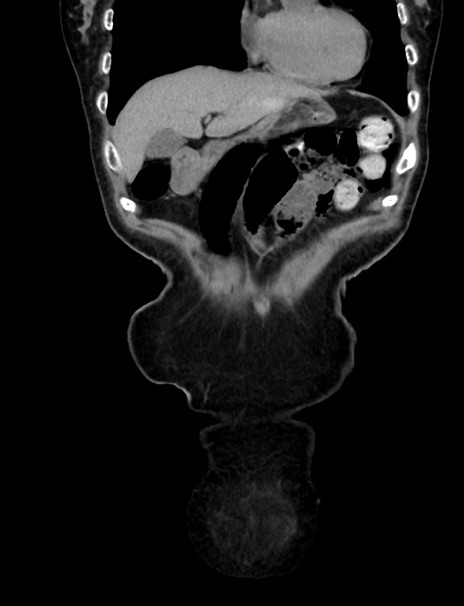

症例33(冠状断像)

【症例】70歳代 女性

【主訴】心窩部痛

【現病歴】延髄病変の精査・加療にて神経内科入院中。本日より心窩部痛あり。

【身体所見】右下腹部を中心に圧痛と反跳痛あり。

【データ】WBC 10900、CRP 0.02